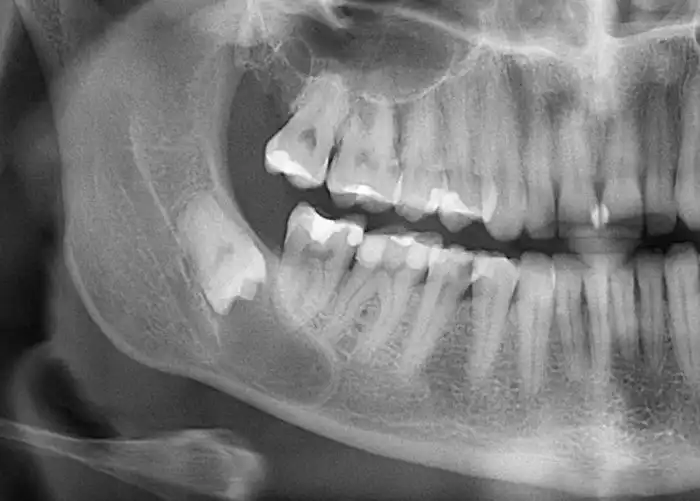

Зубы мудрости

Необходимы были для более качественного пережевывания грубой пищи. Стали пропадать опять же из-за смены рациона питания. Мясо стали перерабатывать. Необходимость в мощных челюстях для перемалывания корней и жестких стеблей отпала. И зубы мудрости, которые сейчас в том или ином количестве имеются у половины населения, постепенно исчезнут совсем.